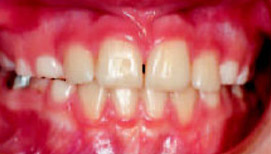

Рис.6: Через 2 недели после начала лечения

Обратное резцовое перекрытие часто сочетается с мезиальным смещением нижней челюсти, при определении конструктивного прикуса нижнюю челюсть необходимо установить в ретро-положение. Кроме того, чтобы найти оптимальное положение зубов, необходимо обратить внимание на характер окклюзионных контактов.